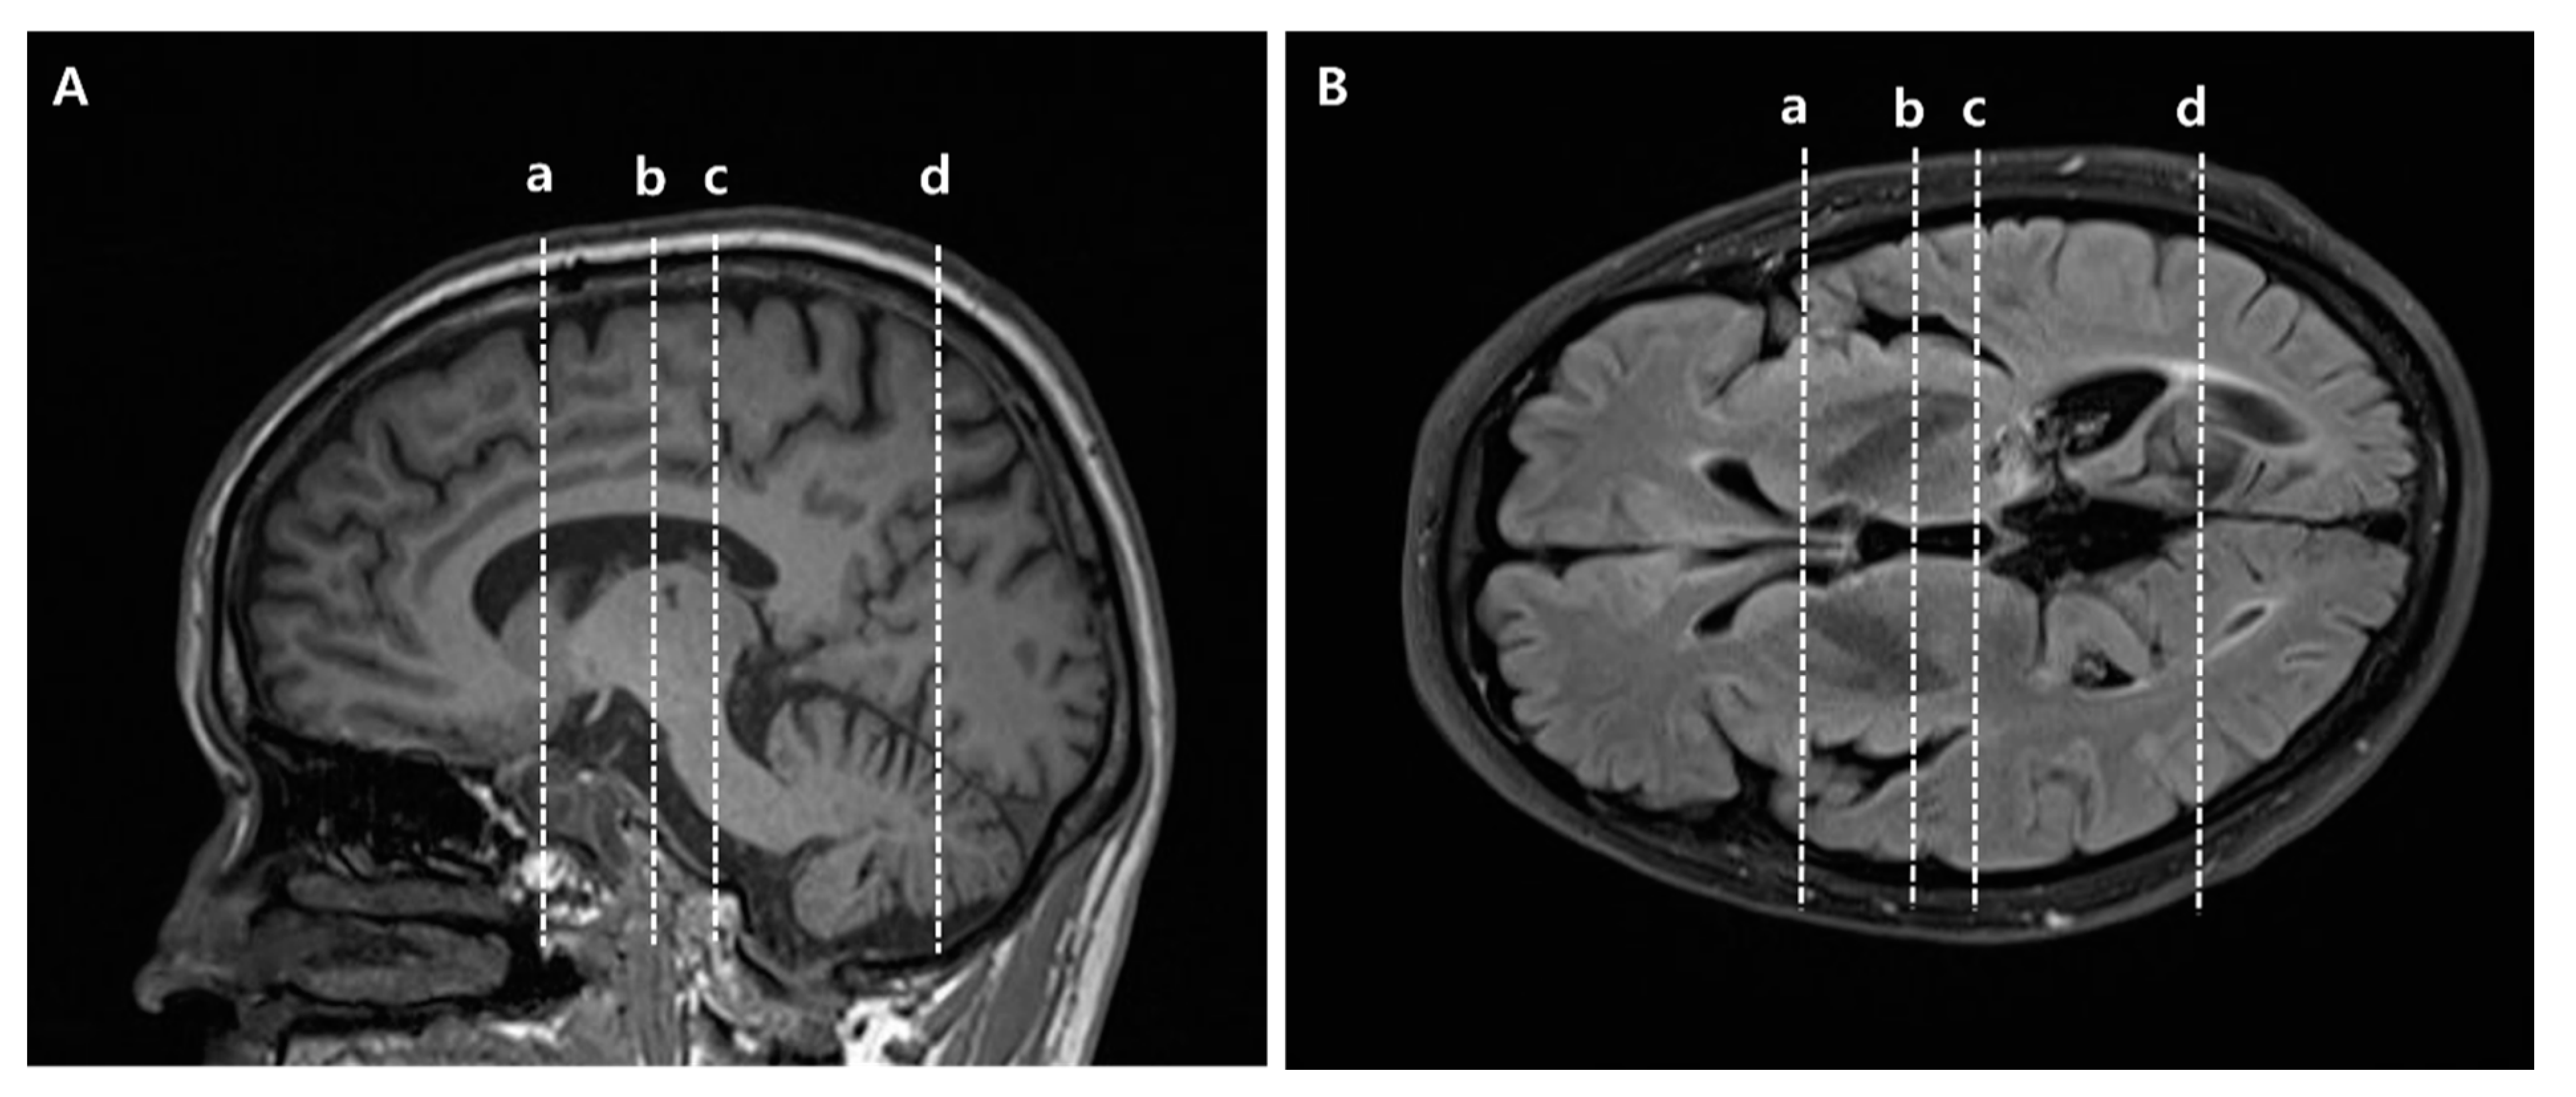

2.3. Diffusion Tensor Tractography

To reconstruct the CST, the seed ROI was placed on the mid-pons portion of the CST in the axial plane, and the target ROI was the primary motor cortex (Supplementary Materials Figure S1) []. STT was reconstructed using two ROIs, with the seed ROI placed on the posterolateral medulla (posterior to the inferior olivary nucleus, anterior to the inferior cerebellar peduncle, and lateral to the medial lemniscus) in the axial plane, and the target ROI was the primary somatosensory cortex (Supplementary Materials Figure S2) [,]. For reconstruction of the ATR, the seed ROI was located on the anterior part of the thalamus in the coronal plane where the substantia nigra first appears, and the target ROI was at the slice level where the frontal and temporal lobes were separated in the coronal plane (Supplementary Materials Figure S3) []. PTR was reconstructed using two ROIs, with the seed ROI placed on the posterior thalamus at the slice level where the posterior tip of the putamen lies in the coronal plane, and the target ROI was the occipital lobe below the parieto-occipital sulcus (Supplementary Materials Figure S4). To reconstruct STR, the seed ROI was on the middle thalamus in the coronal plane at the midpoint slice level between the ATR and PTR seed ROI, and the target ROI was the entire ipsilateral hemisphere within a transverse section above the corpus callosum in the axial plane (Supplementary Materials Figure S5) []. As the seed and target ROIs of ATR and PTR were complicated, specific anatomical locations are provided in Figure 1. The FA values were measured in the seed ROIs of each tract in both hemispheres, and FN values were measured in both hemispheres of all patients. The normalization ratios for FN and FA values were calculated using the following formula in the CPSP and non-CPSP groups: data of affected side/data of non-affected side []. For the control group, the normalization ratio for FN and FA values was calculated as left/right [].

Figure 1. Specific anatomical locations of seed and target regions of interest (ROIs) of anterior thalamic radiation (ATR) and posterior thalamic radiation (PTR) in slice levels in brain MR images. (A) Sagittal view for ROIs, (B) Axial view for ROIs. (a) Target ROI of ATR where the frontal and temporal lobes are separated. Equivalent slice level to (a) in Supplementary Materials Figure S3. (b) Seed ROI of ATR located on the anterior part of the thalamus where the substantia nigra first appears. Equivalent slice level to (b) in Supplementary Materials Figure S3. (c) Seed ROI of PTR located on the posterior part of the thalamus, where the posterior tip of the putamen lies. Equivalent slice level to (c) in Supplementary Materials Figure S4. (d) Target ROI of PTR located below the parieto-occipital sulcus. Equivalent slice level to (d) in Supplementary Materials Figure S4.